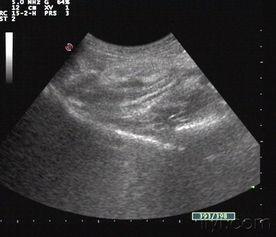

阑尾炎照片,直观解析与病例分析

说到阑尾炎,这可是个让人一听就心头一紧的话题。想象肚子突然一阵剧痛,紧接着就是翻江倒海的难受,这滋味儿,简直了!今天,就让我带你一起,通过阑尾炎的照片,来了解一下这个让人头疼的小家伙。阑尾炎,你长什么样?阑尾炎,这个名字听起来就让人心生恐惧。那么,阑尾炎的照片又会是什么样子呢?首先,我们要知道,阑尾炎是一种炎症性疾病,通常发生在人体的阑尾部位。阑尾,这个看似不起眼的小器官,位于人体右下腹,连接着盲肠。当阑尾发炎时,它的外观会发生一些变化。通过一些医学图片,...